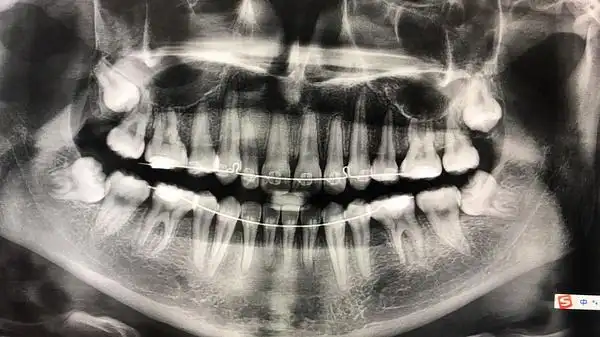

刚刚拍的牙片

洗牙的时候偷偷用手机拍下了我的牙片,不知道怎么样,自我感觉还挺正的